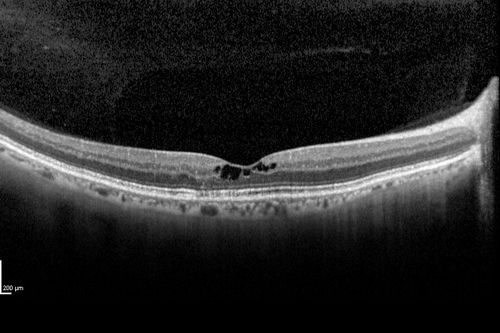

Macular Telangiectasis (Group 2a Juxtafoveal Telangiectasis) Decreased Fundus Autofluorescence

63-year-old woman has juxtafoveal retinal telangiectasis in both eyes.  She notices her vision a little worse with more distortion and change over the last six months.

VISUAL ACUITY:  OD 20/40,  OS 20/40.